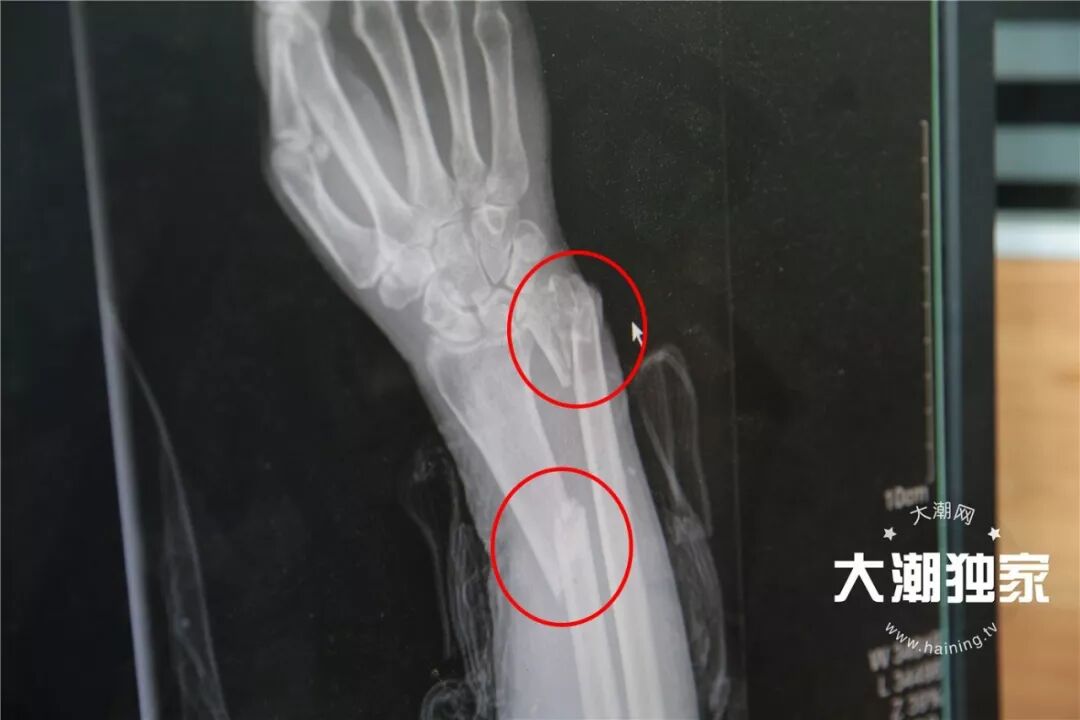

老太当时右手腕有点骨折额头磕在台阶上,流着血

右前臂有2处骨折